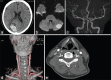

Figures